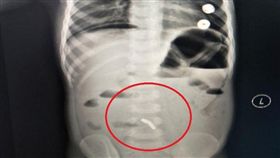

少年誤吞近100顆強力磁鐵!醫急切腸救命

紐西蘭一名 13 歲少年因腹痛4天送醫,經檢查後驚見...

驚!男童「吞61顆巴克球」腸道竟14處穿孔

孩童亂吞東西可能有生命危險,家長要多注意!近日中國一...